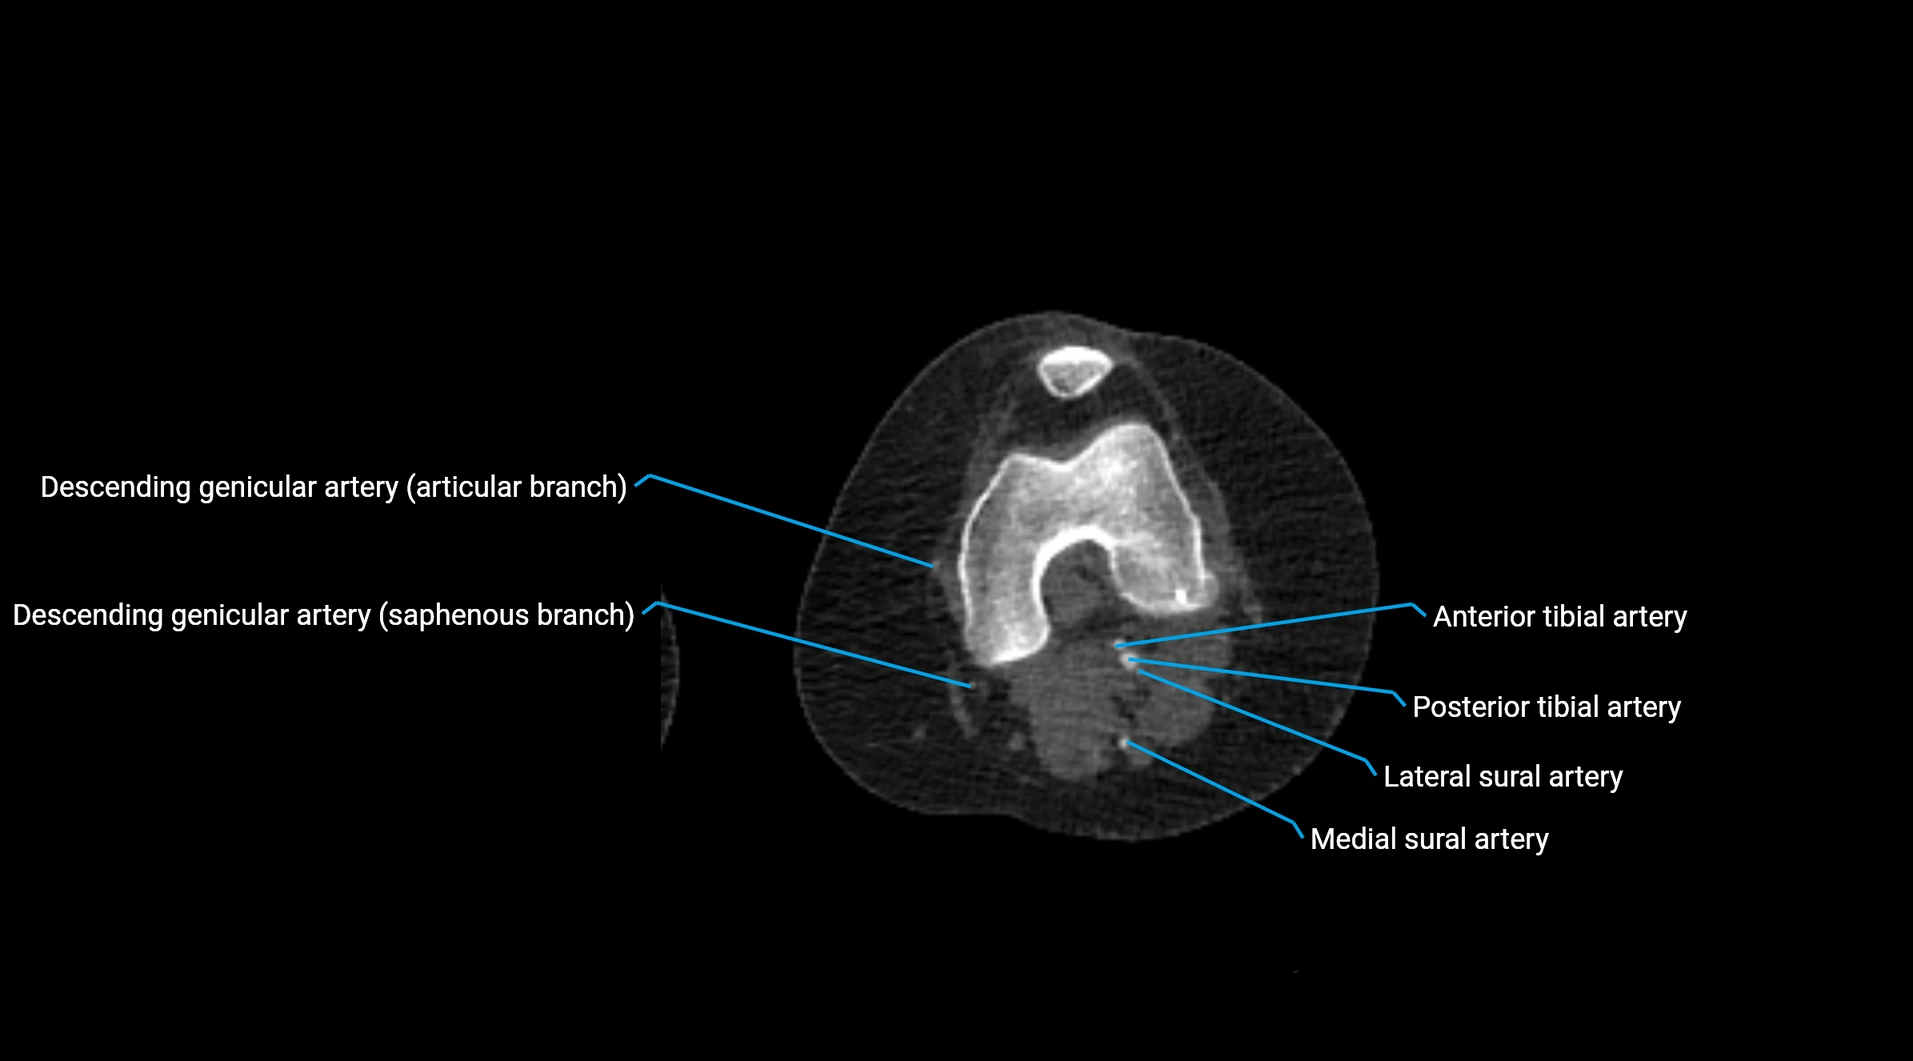

CT Appearance

Contrast-enhanced CT (CTA):

• Gold standard for abdominal aortic imaging

• Provides excellent detail of lumen, wall, aneurysm, thrombus, and branch vessels

• Multiplanar and 3D reconstructions help in aneurysm measurement, stent graft planning, and dissection evaluation

• Detects acute rupture, traumatic injury, or occlusion with high sensitivity